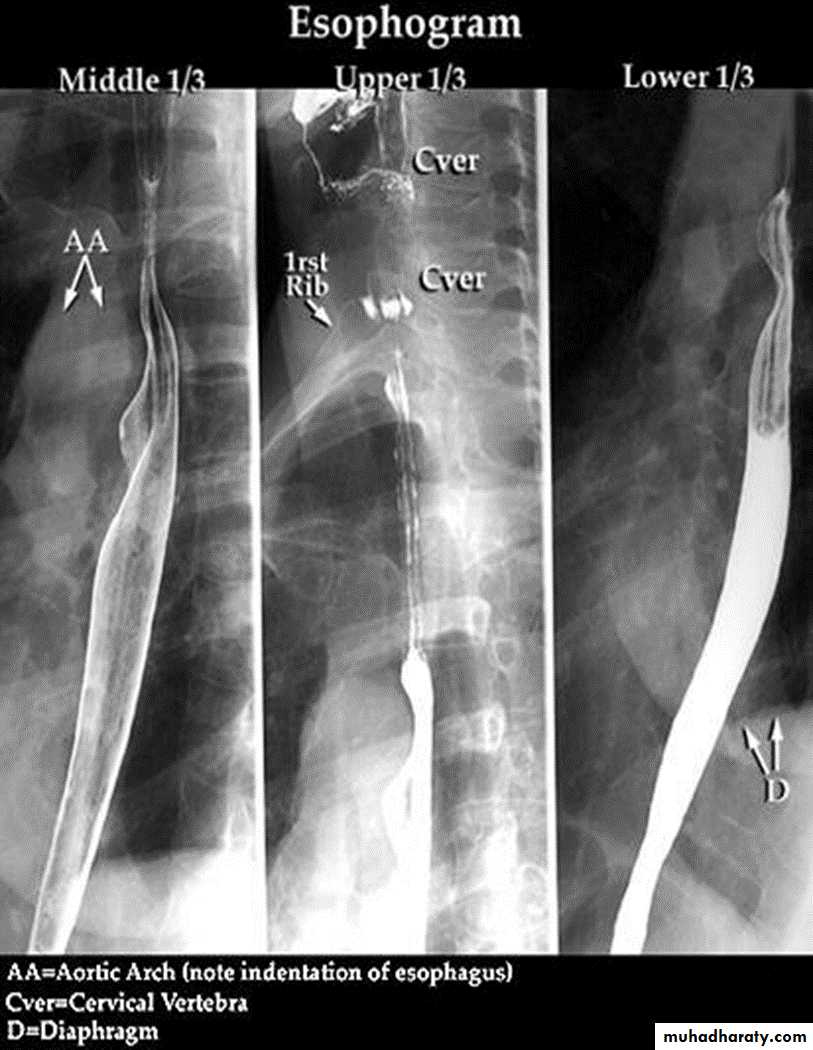

The Normal Anatomy: *Long tubular structure * Length 25-30 cm* Start at level of C5 ( Crico-pharengeal)* End – Cardiac sphincter* Three portions Cervical Thoracic Abdominal* Normal Mucosal pattern (DC) thin regular longitudinal Parallel Numbers of lines ( 4-5 )

Areas of normal Narrowings:- body of the cervical vertebra - AA- LT atrium- diaphragmatic hiatus